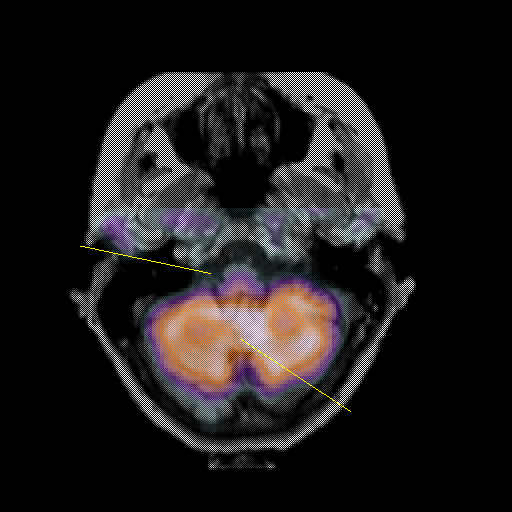

overlay: Slice 11

Slice 11

MRCBFCBF with

Pointers

Labeled